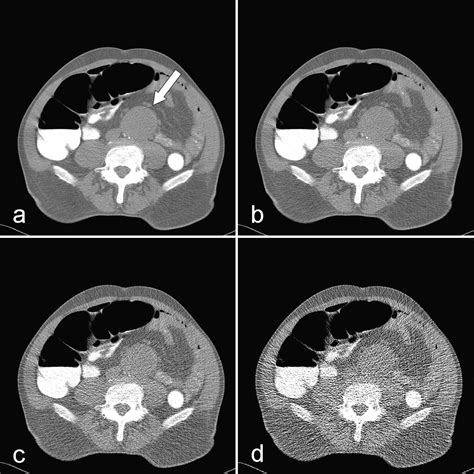

At its core, Ct Scan Colonography is a specialized radiological imaging test that produces 2D and 3D images of the large intestine. Unlike a standard colonoscopy, which involves physical exploration of the bowel, this procedure relies on computed tomography (CT) to create a detailed internal map. The process requires the patient’s colon to be inflated with air or carbon dioxide to ensure the walls of the bowel are fully distended, which allows the CT scanner to capture clear, unobstructed views of the lining.

• Imaging: The patient will hold their breath for brief intervals while the scanner captures high-resolution images, usually in two positions: once while lying on their back and once while lying on their stomach (or side).

The primary advantage of Ct Scan Colonography is its ability to screen for polyps and masses with a high degree of sensitivity. Because it is less invasive, it carries a significantly lower risk of complications, such as bowel perforation. It is an ideal option for individuals who prefer to avoid the risks associated with moderate to deep sedation, such as those with certain heart or lung conditions.

However, it is important to acknowledge the limitations. The most notable limitation is that while the scan can identify suspicious polyps, it cannot remove them. If a polyp is detected during the scan, the patient will need to undergo a traditional colonoscopy to biopsy or remove the growth. Furthermore, because the scan utilizes ionizing radiation, it is generally recommended to discuss the cumulative exposure with a healthcare provider, especially if frequent screenings are anticipated over a lifetime.